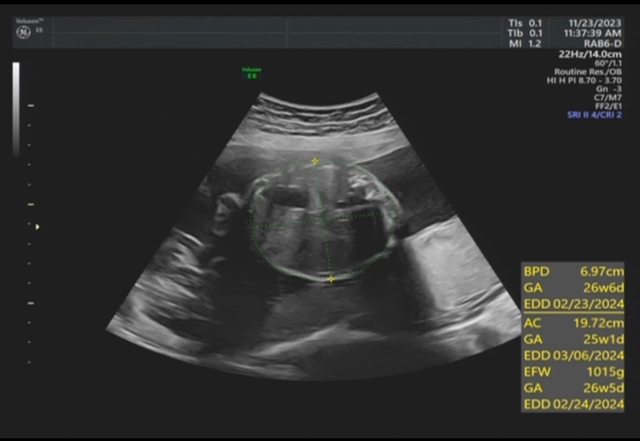

昨天去產檢,醫生覺得寶寶的胃偏大之後要注意觀察 我搜尋了一下好像只有看到胃太小的文,請問大家有沒有遇過類似情況? 我後來看了一下22週的高層次照片,那時候寶寶也是胃大大的,但那時只說是寶寶可能剛 吃飽 https://i.imgur.com/amlKp09.jpg

每一胎的狀況真的不一樣,這次第二胎先歷經羊水少週數小三週,到現在追到剩小一週, 但昨天醫生又提醒胃好像偏大,只希望二寶可以健康平安出生~ -- ※ 發信站: 批踢踢實業坊(ptt-web.org.tw), 來自: 101.12.24.40 (臺灣) ※ 文章網址: https://ptt-web.org.tw/BabyMother/M.1700797726.A.8D2